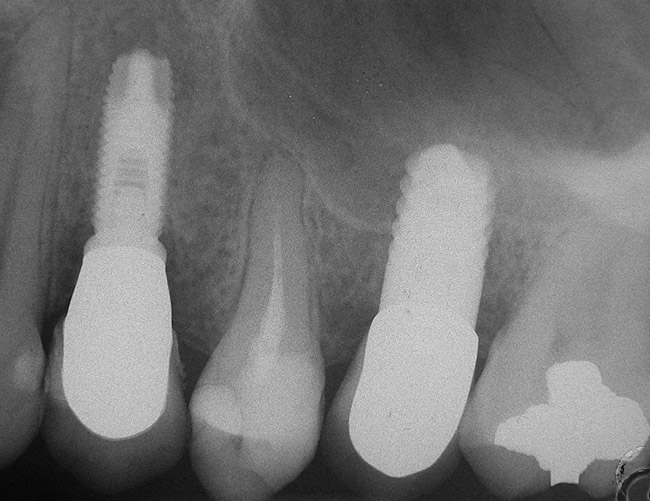

At the time of surgery, the tooth was extracted without harvesting any mucosal flap because the implant site was prepared by means of a pilot drill bur (Figure 13) and alternating osteotomes (Figure 14A and Figure 14B). The implant was positioned and showed primary stability. The implant was loaded 2 days after surgery. Then, splinted PFM crowns supported by custom gold abutments were delivered. At 6 months posttreatment, the radiograph revealed no bone resorption and the clinical result was optimal (Figure 15A and Figure 15B).

Figure 15B Posttreatment radiograph, 6 months after the initial surgery.

Figure 15  Posttreatment radiograph, 6 months after the initial surgery.

Figure 15b